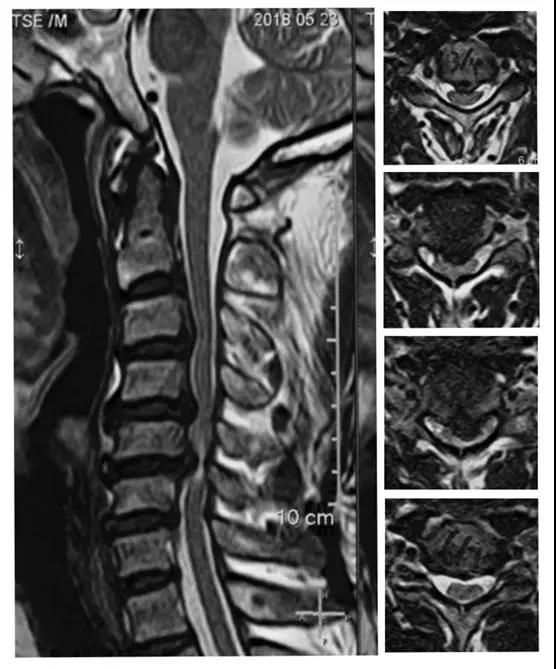

颈椎间盘切除人工椎间盘置换手术-mobi-c

患者:男,31岁

主诉:颈肩痛伴右上肢放射痛、麻木20天。

查体:

右侧臂丛神经牵拉实验+。会阴部及四肢皮肤感觉正常。四肢肌肉无萎缩,肌力正常。双侧肱三头肌减反射减弱,余生理反射正常。双侧病理征阴性。双侧髌阵挛、踝阵挛未引出。

诊断:颈椎间盘突出症(C5/6)

术前X线正侧位片

术前MRI